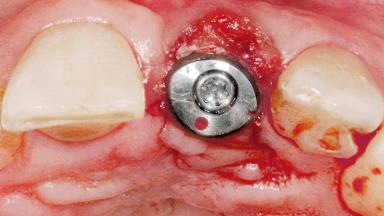

Late Flapless Placement of an Implant in a Maxillary Left Central Incisor Site

A 39-year-old male patient presented with a chief complaint of discomfort and gingival discoloration around his maxillary left central incisor. He was in good general health and was a non-smoker. His past dental history was significant because of the traumatic fracture of tooth 21 in a sporting accident at age 13. Initial dental treatment included endodontic therapy and a full-coverage restoration. The patient became symptomatic 5 years later, when structural failure of the tooth resulted in the dislodgment of the crown. Endodontic retreatment, apical surgery, and post-and-core restoration were performed.

Type of Implants One-Piece